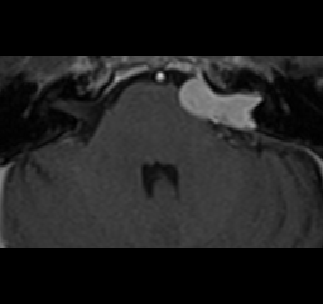

Recently, deep learning methods have achieved state-of-the-art performance in many medical image segmentation tasks. Many of these are based on convolutional neural networks (CNNs). For such methods, the encoder is the key part for global and local information extraction from input images; the extracted features are then passed to the decoder for predicting the segmentations. In contrast, several recent works show a superior performance with the use of transformers, which can better model long-range spatial dependencies and capture low-level details. However, transformer as sole encoder underperforms for some tasks where it cannot efficiently replace the convolution based encoder. In this paper, we propose a model with double encoders for 3D biomedical image segmentation. Our model is a U-shaped CNN augmented with an independent transformer encoder. We fuse the information from the convolutional encoder and the transformer, and pass it to the decoder to obtain the results. We evaluate our methods on three public datasets from three different challenges: BTCV, MoDA and Decathlon. Compared to the state-of-the-art models with and without transformers on each task, our proposed method obtains higher Dice scores across the board.